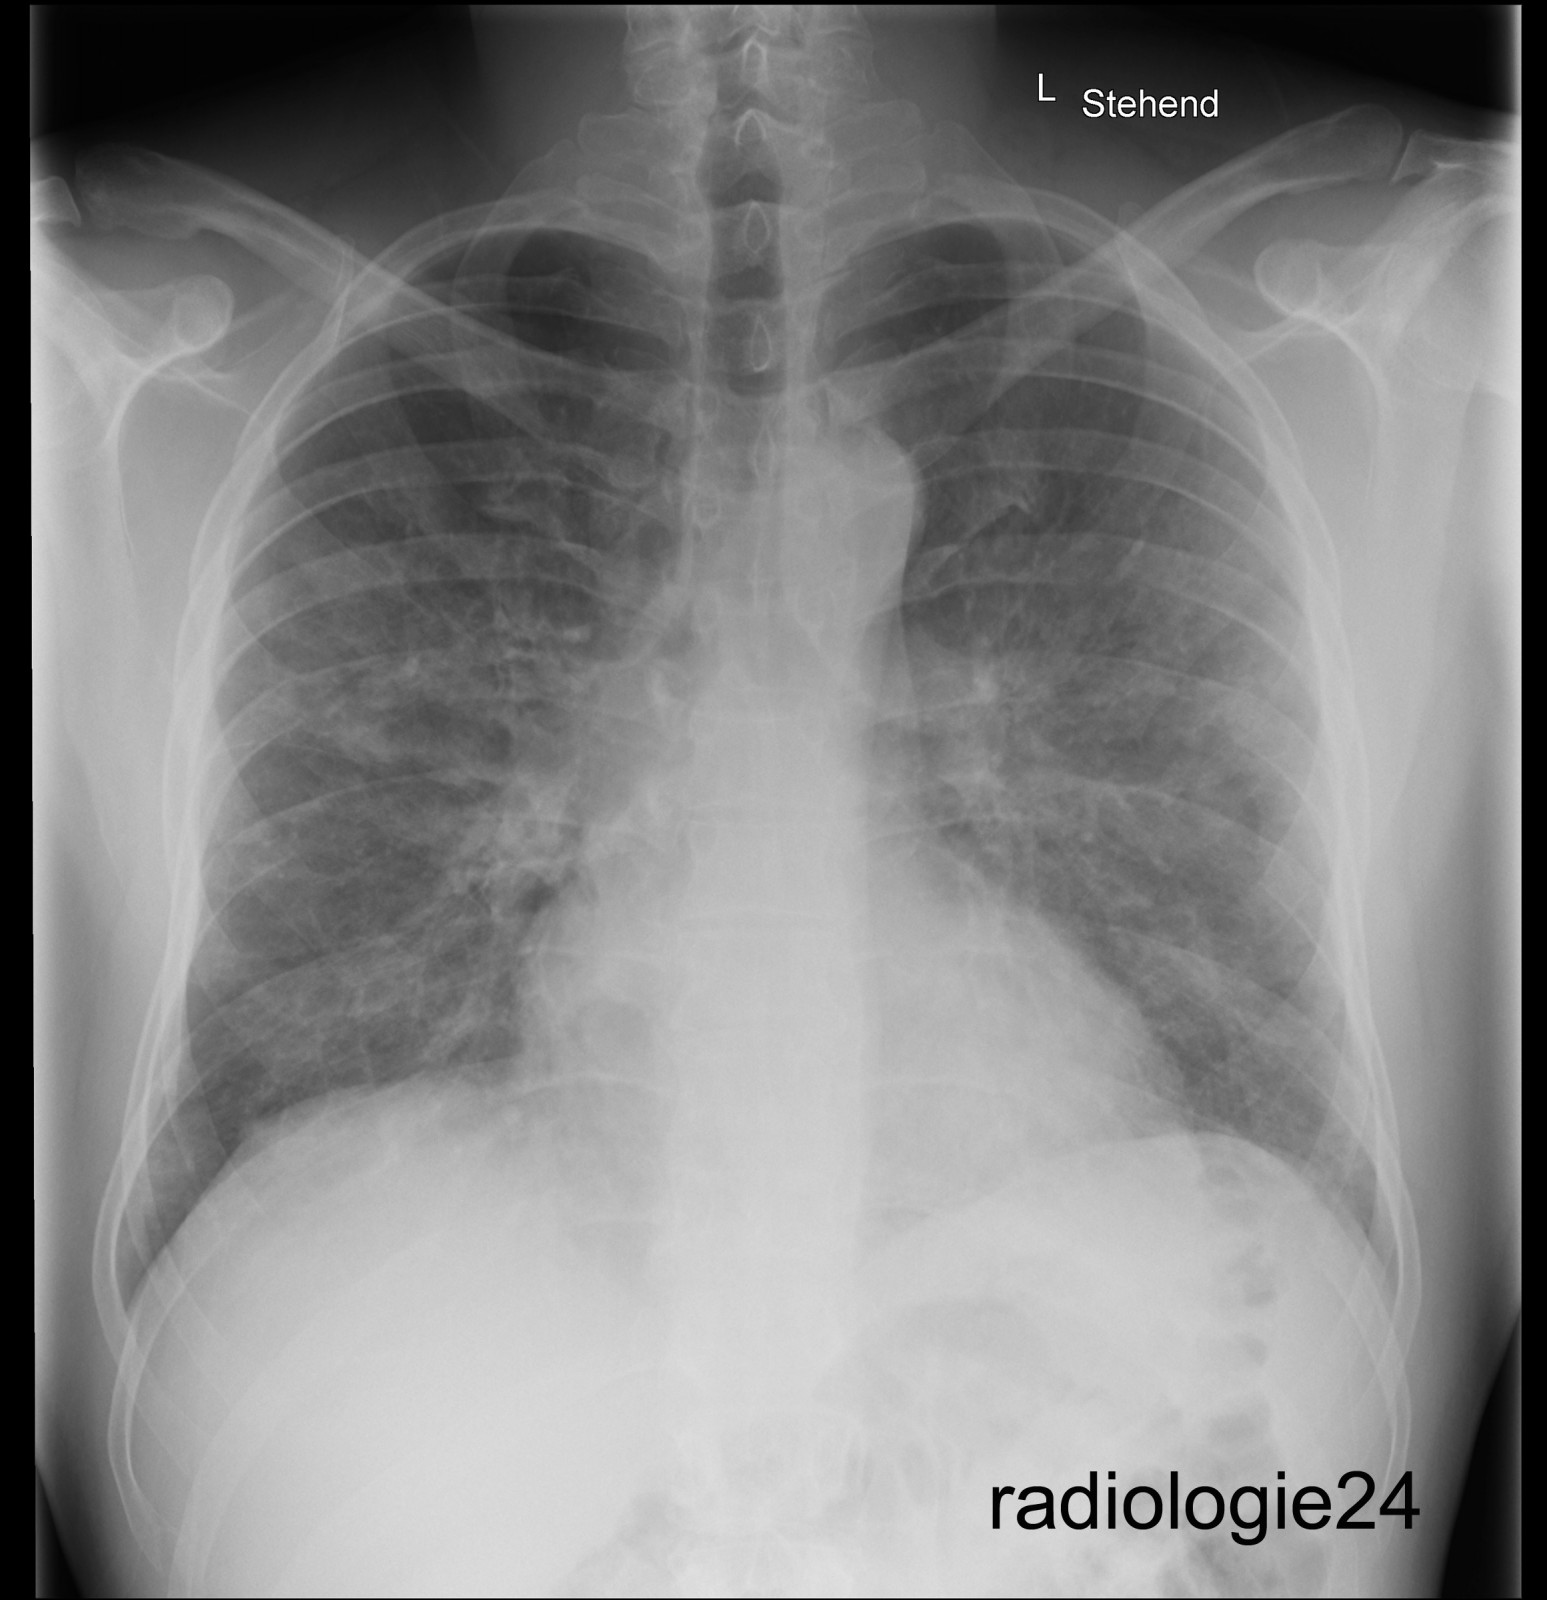

Röntgenfall des Monats August 2018 mit Auflösung

40 jähriger Patient Triathlon Sportler. Bei einem Wettkampf muss der Patient wegen akut auftretender Dyspnoe nach dem Schwimmen, die Disziplin des Fahrradfahrens abbrechen und kann den Triathlon nicht beenden. Einlieferung in die Notaufnahme des nächstliegenden Spital. Ihre Diagnose? Weitere radiologische Diagnostik notwendig?

Bild vergrössern